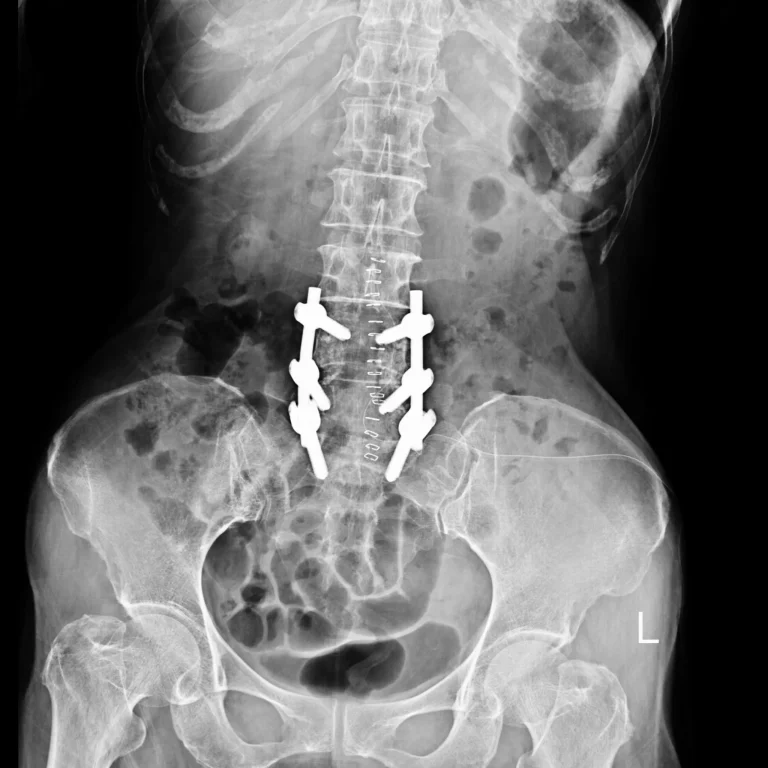

X-ray showing spinal fixation hardware in the lower back.

Spinal Fusion

Common Problems, What Surgeons Don't Always Tell You

Permanently fuses vertebrae using screws, rods, and cages. It eliminates natural spinal motion and causes adjacent segment disease.